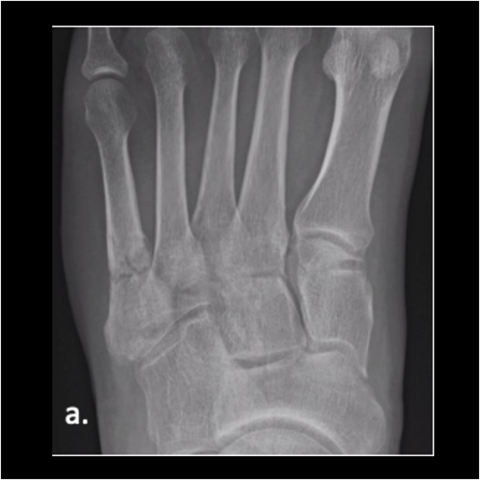

Figure 3a

Figure 3a. A 28-year-old Army officer injured during combatives was able to walk 2 days post-surgery. He started wearing his Army boots 2 weeks after surgery and completed Sapper School 10 weeks after surgery. He then went to Special Forces training within 6 months postop. The patient never had any pain after surgery. Here is the foot when the patient got injured.